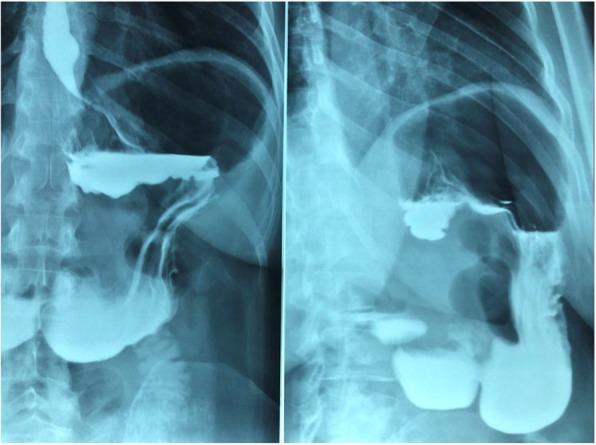

机器人辅助巨大食管旁疝修补术:一例病例报告及文献综述

Robotic voluminous paraesophageal hernia repair: a case report and review of the literature.

To investigate robotic paraesophageal hernia repair, a literature search was conducted using PubMed with the following key words: mini invasive surgery, robotic surgery, hiatal hernia, and Nissen fundoplication. We present the case of a 44-year-old Italian woman with a 20-year history of gastroesophageal reflux disease refractory to medical treatment, who underwent robotic Nissen fundoplication. In our center, we use the da Vinci® Xi™ Surgical System, which is an advanced tool for minimally invasive surgery.

为了研究机器人辅助食管旁疝修补术,我们使用PubMed进行了文献检索,关键词如下:微创手术、机器人手术、食管裂孔疝和nissen胃底折叠术。我们报告了一例44岁的意大利女性病例,她有20年的胃食管反流病病史,药物治疗无效,接受了机器人nissen胃底折叠术。在我们中心,我们使用达芬奇Xi™手术系统,这是一种先进的微创手术工具。